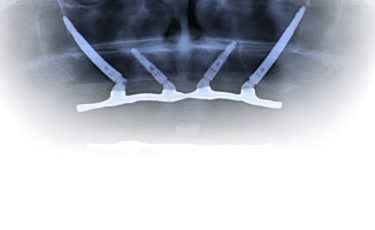

2. Cirurgia de instalação dos implantes zigomáticos

A cirurgia é realizada com todos os cuidados e conforto para o paciente. Dependendo do caso, pode ser indicada sedação consciente ou anestesia associada, para tornar o procedimento mais tranquilo.

Uma vez instalados e bem distribuídos, os implantes zigomáticos servem como pilares de sustentação para uma estrutura metálica (barra ou infraestrutura) sobre a qual será fixada a prótese.